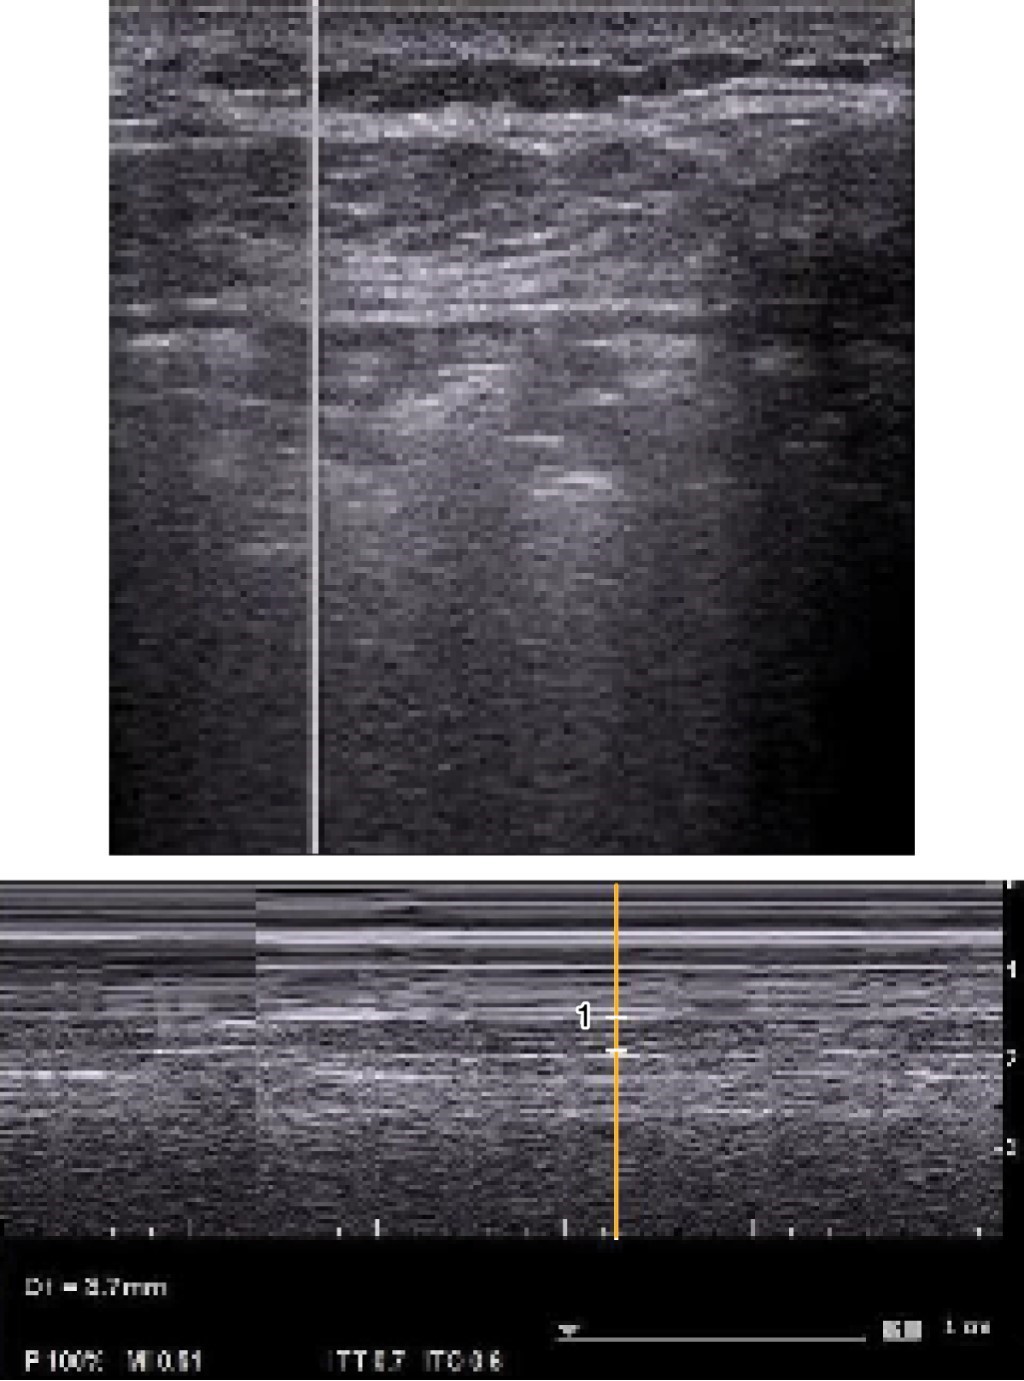

Posterior a la identificación de la consolidación subpleural en modo B (Figuras 1 y 2) se realizará la medida del tamaño de ésta en modo M, colocando el marcador al centro de la consolidación y se procederá a evaluar el movimiento respiratorio cíclico del pulmón y posteriormente se congelará la imagen al observar por lo menos dos movimientos cíclicos y se procederá a la medición al final de la espiración, en sus medidas longitudinal y transversal, colocando el cursor para su medida en mm (Figuras 3 y 4).

Las consolidaciones subpleurales se identificaron como lesiones hipoecoicas localizadas en la región subpleural, para ser más específicos por debajo de la pleura, o bien descritas como "signo de la pleura cortada", las cuales presentan cambios en su tamaño a la inspiración y espiración.

En los pacientes en los que se realizó ultrasonido pulmonar tanto en modo B como en modo M se obtuvieron diferentes imágenes y se logró medir el tamaño de la consolidación, obteniendo una mejor calidad y tamaño en las imágenes en modo M, principalmente en aquellos pacientes en los que se utilizó un transductor convexo. Todos los pacientes en los que se identificaron consolidaciones subpleurales de mayor tamaño cursaban con cuadros graves de la enfermedad, como síndrome de distrés respiratorio severo y aquellos que no se encontraban intubados, pero en los que se identificaron consolidaciones subpleurales, tuvieron mal pronóstico y evolucionaron a deterioro y finalmente requirieron manejo avanzado de la vía aérea.

Debido a que en modo B con el transductor convexo es difícil medir y poder ser más objetivo en la magnitud de estas consolidaciones, propusimos la medición de dichas consolidaciones con un transductor convexo y en modo M.

La técnica que proponemos es medir dichas consolidaciones principalmente en modo M, ya que en modo B no se pueden identificar claramente los bordes de la consolidación, lo cual dificulta la medición durante la inspiración y espiración, siendo este último el valor que se tomará en cuenta, como se observa en las imágenes.

Figura 2